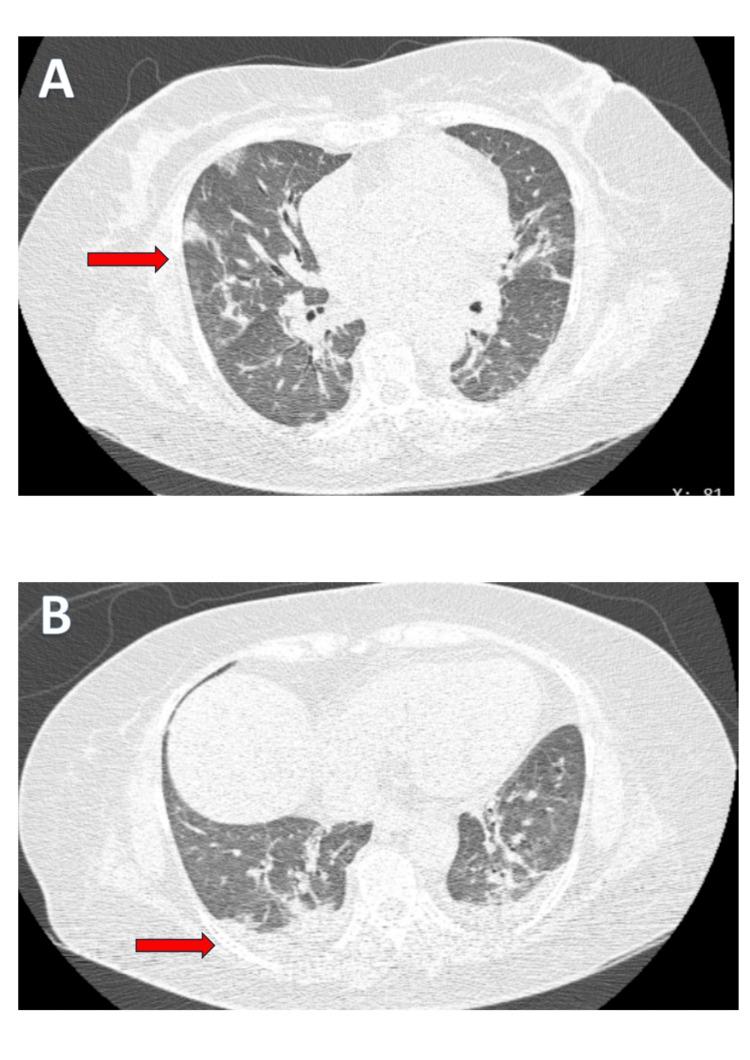

Scrub typhus, caused by , transmitted through bites from infected chiggers (larval mites), is a common infection in the Asia-Pacific region, including the Maldives, and typically presents with fever with myalgia, rash, eschar, and internal organ involvement. Pulmonary complications like severe pneumonia are less common but can be life-threatening. We report a case of a 51-year-old woman with underlying hypertension and rheumatoid arthritis on immunosuppressive therapy, who presented with high-grade fever, dry cough, and worsening shortness of breath. Physical examination revealed an eschar on her left thigh and crackles at both lung bases. Chest imaging showed bilateral ground-glass opacities consistent with interstitial pneumonia. Serological testing confirmed scrub typhus infection. She was treated with a combination therapy of doxycycline and azithromycin, along with supportive care in the ICU, resulting in full recovery. This case highlights the need to consider scrub typhus in patients with severe pneumonia from endemic areas, especially in those with underlying health conditions, to ensure timely diagnosis and treatment, which is critical for reducing complications of pneumonia and morbidity.

恙虫病由恙虫病东方体引起,通过被感染的恙螨(幼虫螨)叮咬传播,在包括马尔代夫在内的亚太地区是一种常见感染,通常表现为发热伴肌痛、皮疹、焦痂和内脏器官受累。像重症肺炎这样的肺部并发症不太常见,但可能危及生命。我们报告一例51岁女性病例,该患者患有高血压和类风湿关节炎,正在接受免疫抑制治疗,出现高热、干咳和进行性加重的气短。体格检查发现其左大腿有一个焦痂,双肺底部有啰音。胸部影像学显示双侧磨玻璃影,符合间质性肺炎表现。血清学检测确诊为恙虫病感染。她接受了多西环素和阿奇霉素联合治疗,并在重症监护病房接受支持治疗,最终完全康复。该病例强调,对于来自流行地区的重症肺炎患者,尤其是有基础健康问题的患者,需要考虑恙虫病,以确保及时诊断和治疗,这对于减少肺炎并发症和发病率至关重要。